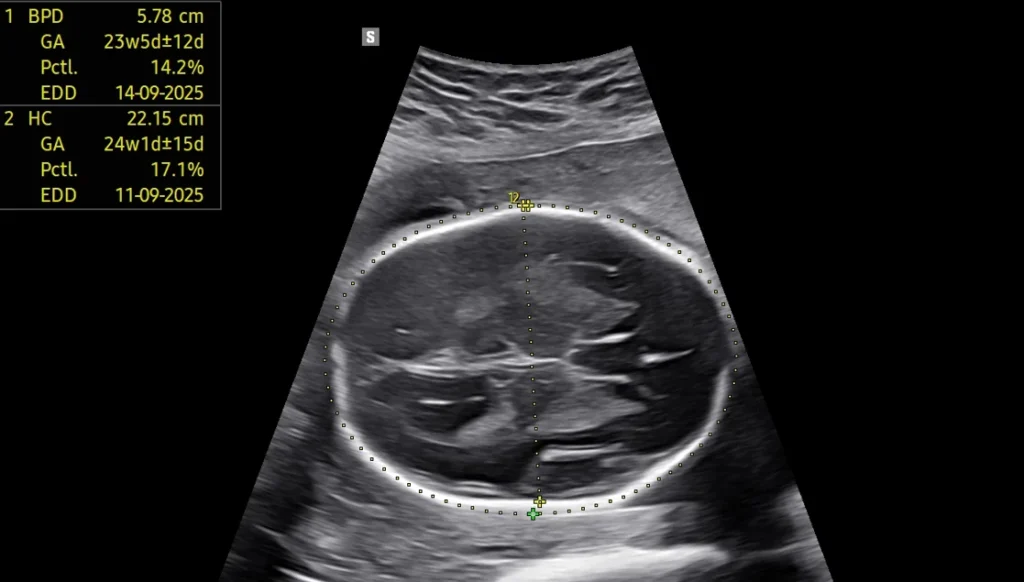

Level II Detailed Anomaly Scan (18–22 weeks)

Most important Fetal scan:

• Head-to-toe structural evaluation

• Heart, brain, spine, face, limbs, kidneys

• Placenta, amniotic fluid & cervix

• Soft markers review

Fetal Well-Being & Biometry

Growth scans, BPP, AFI, interval growth patterns, and third-trimester monitoring.